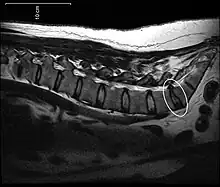

[1] A disc protrusion is a medical condition that can occur in some vertebrates, including humans, in which the outermost layers of the anulus fibrosus of the intervertebral discs of the spine are intact but bulge when one or more of the discs are under pressure.

Many disk abnormalities seen on MRI that are loosely referred to as "herniation" are actually just incidental findings. These may be unrelated to any symptoms and are just bulges of the anulus fibrosus. Jensen and colleagues, in an MRI study of the lumbar spine in 98 asymptomatic adults, found that in more than half, there was a symmetrical extension of a disc (or discs) beyond the margins of the interspace (bulging). In 27 percent, there was a focal or asymmetrical extension of the disc beyond the margin of the interspace (protrusion), and in only 1 percent was there more extreme extension of the disc (extrusion or sequestration). These findings emphasize the importance of using precise terms in describing the imaging abnormalities and evaluating them strictly in the context of the patient's symptoms.[1]

A disc protrusion may progress to a spinal disc herniation, a condition in which there is a tear in the anulus fibrosus.[2] The most common area to have a disc protrusion is in the Lumbar Spine, specifically L-5.[2]